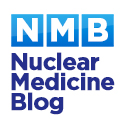

Finally, a delayed phase SPECT-CT of both knees is performed. Our CT scans are performed with an extended Hounsfield scale to reduce metallic artefact.

The tibial component is loose when there is focal increased tracer uptake at the sites of maximal mechanical stress; usually at the tip of the tibial component and at the contralateral tibial tray. Loosening of the femoral component is often associated with increased uptake adjacent to the posterior aspects of the condyles, adjacent to the bone prosthesis interface. The CT component will show a periprosthetic lucency that is greater than 2mm in width, with irregular margins, at the site of increased bone uptake.

Infected prostheses usually have increased activity in dynamic and blood pool phases throughout the bone surrounding the infected prosthesis. On SPECT-CT there is diffuse increased uptake around the bone prosthesis interface, with periosteal reaction, soft tissue oedema, soft tissue abscesses or joint effusions.